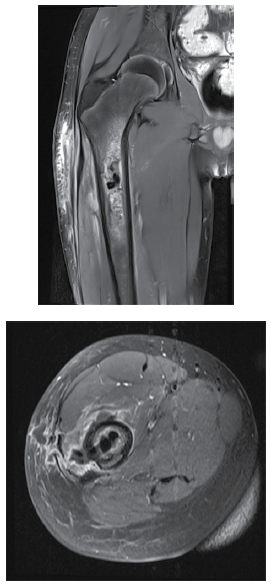

Considere um paciente, vítima de queda de bicicleta há 4 meses, com trauma e laceração na coxa, que vem piorando. Ao exame no pronto atendimento, as imagem são as seguintes:

As imagens apresentadas sugerem: